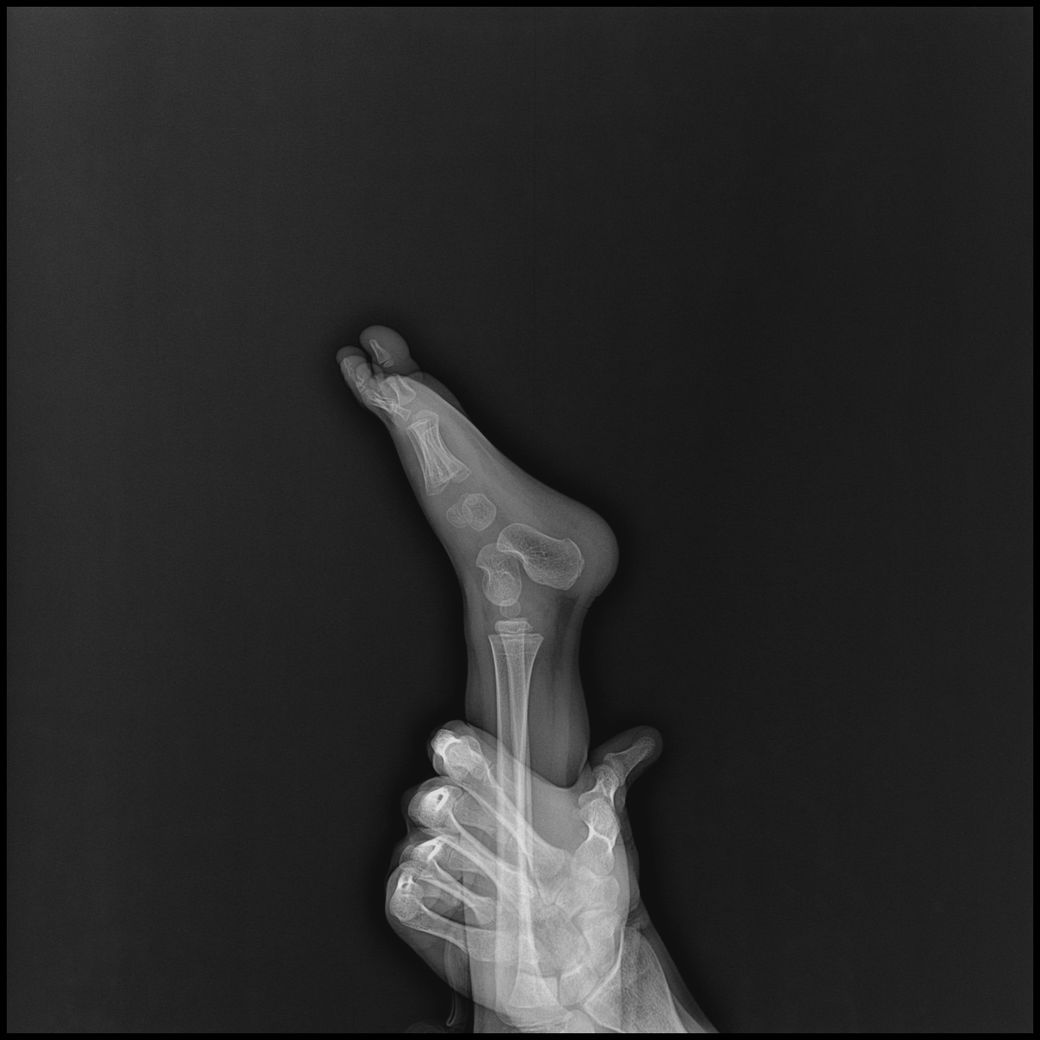

아기 손발 엑스레이를 찍게되었는데요.

손목, 발목까지 6-8장 찍기로 안내받았으나,

고관절,복부일부,생식기등 민감부위등이 추가로 촬영되었고

발도 다리가 다 찍혔고 총 19장이 찍혔습니다.

- 발~다리사진 : 10장

• 2번 째 사진